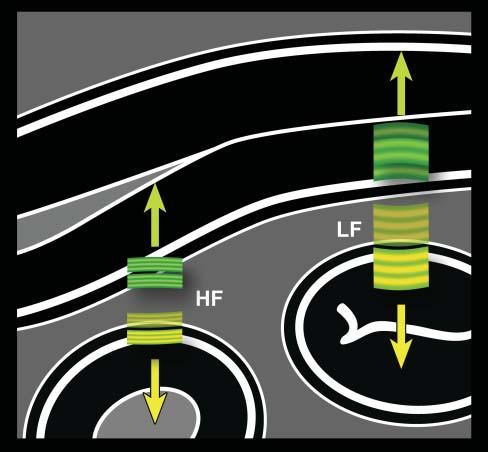

Toproducean image,thefirstpiezoelectriccrystals arestimulatedtogenerateashortultrasoundpulse–comprisingthreetofourwaves–thattravelsthrough tissueinterfacestoproducethousandsofechoes thataresentbacktotheprobe(Figure1.1).Shortly

afterward,anewultrasoundpulseleavestheprobe atadifferentangle,generatinganewsetofechoes thatreturntothesecondseriesofcrystals.Assuminga constantwavepropagationspeedof1,540m/sinsoft tissues,eachoftheseechoescanbelocatedprecisely alongthetrajectory,dependingonthetimeinterval betweenthedepartingwaveandthereturningecho (Hangiandreouetal.2003).Hundredsofwavelinesare producedthisway,scanningtissuesathighspeedto produceover30images/s,eachonecontainingthousandsofpixelsdescribingtheacousticcharacteristics ofthescannedtissues.

Figure1.1. Ultrasoundpropagationandimageformation. Eachultrasoundimageisformedbytheadditionofhundredsofindividualscanlines.Eachlineisproducedaftera singleultrasoundpulse(inyellow)isemittedbythetransducer.Asthispulsepropagatesthroughsofttissues,many echoes(ingreen)aregeneratedatinterfacesofdifferentacousticimpedance(suchashepatocytes–connectivetissue),producinganimageofvariableechogenicityandechotexture. Eachechoisanatomicallylocalizedbasedonthetimeinterval betweentheemittedpulseanditsreception.Afteraspecific time,anewpulseisemittedalonganadjacentline,producing anadditionalscanline.Scanlinesaregeneratedveryrapidly andsuccessively,producing15–60images/s,allowing“real time”ultrasonography.

Figure1.5. Ultrasoundfrequencyversusaxialresolution. Thehigherthefrequency,theshorterthepulse.Becausethe lengthofthepulsedoesnotchangeindepthorafterinteractionwithtissues,high-frequency(HF)echoes(ingreen)that comebacktothetransducerarebetterdiscriminatedbythe system.Closelyassociatedinterfaces,suchassmallintestinal walllayers,arethenbetterrepresented.Conversely,echoes fromcloselyalignedlayersgeneratedbyalow-frequency(LF) pulse(inyellow)partlyoverlapandareinterpretedbythesystemasoriginatingfromasingleinterface.Thisphenomenon isexaggeratedinthisillustrationforbettercomprehensionof thisimportantconcept.

missingalesionthatisadjacenttoanormalstructure. Thespatialresolutionalongthepathoftheultrasound beam–the x-axis–isdeterminedbythelengthof thepulse,whichinturnisrelatedtowavefrequency (Figure1.5).Astheultrasoundfrequencyremains constantwithdepth,sodoestheaxialresolution. Conversely,lateral(y-axis)andslice-thickness(z-axis) resolutionsvarywithdepthastheultrasoundbeam changesinshapetonarrowatthelevelofthefocalzone (Figure1.6).Foragivenprobe,theaxialresolutionis